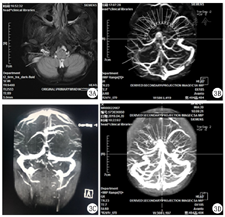

入院治疗:给予一级护理,血氧心电监护,测血压(右侧腘窝血压测不出),嘱卧床,抬高右下肢,局部保暖,给予美罗培南抗感染,阿司匹林肠溶片(国药准字:H13021127,石药集团中诺药业有限公司),25 mg/次,口服,1次/d、低分子肝素钙(国药准字:H20010300,海南通用同盟药业有限公司),100 IU/kg,肌肉注射,每12小时1次、前列地尔(国药准字:H20103101,西安力邦制药有限公司),1 ml,静脉注射,1次/d,抗凝改善循环,帕拉米韦(国药准字:H20130029,广州南新制药有限公司)抗病毒等治疗。入院第2天,患儿仍有反复发热,查体双眼结膜充血,换予美罗培南(国药准字:J20140170,Sumitomo Dainippon Pharma Co Ltd)联合替考拉宁(国药准字:H20093651,浙江海正药业股份有限公司)抗感染治疗,同时予静脉注射人免疫球蛋白(国药准字:S10970032,华兰生药工程股份有限公司),2 g/kg支持治疗。入院第3天患儿仍有反复发热,完善支气管镜检查及肺泡灌洗术,可见各支开口黏膜粗糙,少量稀白分泌物附着,右肺下叶分泌物较多,局部灌洗右肺下叶后可见较多稀白分泌物,管壁毛糙(图2A、图2B)。查下肢血管B超示右侧髂总动脉,髂内动脉起始段、髂外动脉、股总动脉、股浅动脉近心段、股深动脉起始段、腘动脉、胫前动脉、胫后动脉内径、肌间动脉、足背动脉管壁僵硬,管腔内均可见暗淡回声充填,血流信号缺失。全腹部CT示右髂血管密度增高,考虑闭塞性动脉炎。予全身麻醉下行股动脉切开取栓术,分别于股动脉远端、股动脉近端、股深动脉远近端取出长度分别为5.0、4.0、0.5、0.5 cm的血栓(图2C)。入院第4天,患儿体温逐渐正常,右下肢疼痛好转,查体:右小腿中远端及足部皮温暖,可触及明显足背动脉搏动,右足趾甲红润,充血试验正常,复查双下肢血管B超右侧动脉取栓术后,右侧髂总动脉内中膜略厚,回声稍强,右侧股浅、腘、胫前动脉峰值流速较对侧略低,余未见异常。入院第6天,患儿再次出现发热,头痛,具体性质不详,可耐受,伴嗜睡,仍有咳嗽咳痰,复查D-二聚体8.79 mg/L,血清铁蛋白708.25 μg/L,ESR 41 mm/h;复查胸部CT示大叶性肺炎并大量胸腔积液,胸部B超示双侧胸腔积液(右侧大量,左侧少量),胸腔积液常规、生化、染色、培养未见明显异常。肺泡灌洗液培养示革兰阳性球菌,400 cfu/ml。头颅MRI示右侧乙状窦显影浅淡,MRV颈内静脉未见明确显示,考虑血栓可能,脑实质未见异常(图3A、图3B)。脑脊液常规、生化、染色、培养未见异常。换予亚胺培南西司他丁(国药准字:H20084018,珠海联邦制药股份有限公司)联合阿奇霉素(国药准字:H2000426,东北制药集团沈阳第一制药有限公司)序贯治疗,抗感染,布地奈德(国药准字:H20140474,AstraZeneca Pty Ltd)、异丙托溴铵(国药准字:H20150173,SCS Boehringer Ingelheim Comm.V)联合沙丁胺醇(国药准字:H20160660,GlaxoSmithKline Australia Pty Ltd.)雾化止咳化痰,前列地尔抗凝,贝前列素钠(国药准字:H20083589,北京泰德制药股份有限公司)抗血小板,醋酸泼尼松片(国药准字:H33021207,浙江仙琚制药股份有限公司),10 mg/次,口服,3次/d抗炎,合并中药综合治疗。入院第13天,患儿体温正常,精神好转,咳嗽咳痰较前减轻,复查D-二聚体13.11 mg/L,凝血:纤维蛋白原5.73 g/L,加低分子肝素钙抗凝。入院第21天,复查胸部B超示未见胸腔积液,予醋酸泼尼松片逐渐减量至停药。共住院22 d,病情平稳出院。

出院诊断:大叶性肺炎并胸腔积液;难治性支原体肺炎;右下肢动脉闭塞性栓塞:继发性血栓形成;右侧乙状窦血栓;流行性感冒。随访:院外继续口服阿司匹林、贝前列素钠抗凝治疗,定期来我院中西医结合科随访继续口服中药治疗。出院半年后复查D-二聚体逐渐恢复至正常,复查胸部CT肺部病灶逐渐消失,头颅MRI正常,血栓消失(图3C、图3D),至今无复发。

入院后给予一级护理,低流量鼻导管吸氧,亚胺培南西司他丁联合红霉素(大连美罗大药厂,国药准字:H21021678)抗感染,盐酸氨溴索(Boehringer Ingelheim Pharma GmbH & Co.KG,国药准字:J20140032)化痰,布地奈德、异丙托溴铵联合沙丁胺醇雾化止咳化痰,甲泼尼龙琥珀酸钠(国药准字:H20170197,甲泼尼龙琥珀酸钠)抗炎,多烯磷脂酰胆碱(成都天台山制药有限公司,国药准字:H20057684)保肝,更昔洛韦(湖北科盖药业股份有限公司,国药准字:H10981089)抗病毒治疗。入院第7天患儿体温正常,咳嗽咳痰减轻,精神仍稍差,偶有头痛,具体性质不详,可耐受。复查血常规:WBC 14.21×10 9/L,N% 70.2%,RBC 3.93×1012/L,Hb 11 g/L,PLT 360×109/L。尿常规正常。CRP 0.81 mg/L。ESR 63 mm/h。复查胸部CT示肺炎病灶较前吸收不明显,胸部B超示左侧胸腔积液(微量),完善支气管镜及肺泡灌洗术,镜检可见左肺各支开口黏膜粗糙,少量稀白分泌物附着,右肺开口处黏膜粗糙,红肿,右肺中叶分泌物较多,局部灌洗右肺中下叶后可见较多稀白分泌物。肺泡灌洗液培养示革兰阳性球菌,偶见,白细胞(+++)。脑脊液细胞学常规、生化、染色、培养均正常。头颅CT示右侧横窦走行区局部密度增高,大脑脑沟增宽。头颅MRI/MRV/MRA示右侧颈内静脉、乙状窦及横窦走行区信号增高,MRV示右侧颈内静脉、乙状窦及横窦走行区显影欠佳,考虑血栓形成可能,MRA未见明细异常(图4)。心脏B超未见异常。换予拉氧头孢(国药准字:H10930215,海南海灵化学制药有限公司)抗感染,口服醋酸泼尼松片抗炎,加予胞磷胆碱钠(国药准字:H19993061,山东新体制药股份有限公司)营养神经,右旋糖酐40葡萄糖(国药准字:H51020230,四川科伦药业股份有限公司)抗血栓,低分子肝素钙抗凝治疗。入院第30天复查头颅MRI示右侧颈内静脉、乙状窦及横窦走行区异常信号消失,MRV示右侧颈内静脉、乙状窦及横窦显影欠佳,右侧横窦显影较前增粗。共住院36 d,患儿体温正常,无咳嗽咳痰,神清精神可,无特殊不适出院。